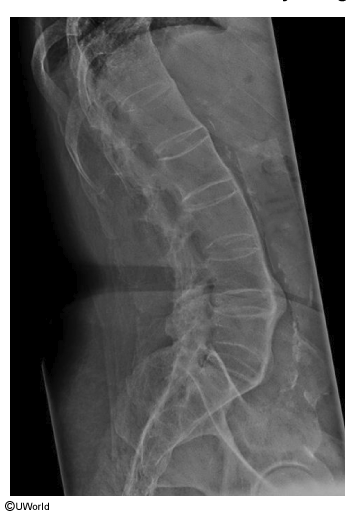

23F progressive low back pain & stiffness over years, worsened recently. pain relieved with activity and ibuprofen. on exam, reduced forward flexion of lumbar spine & tenderness over lumbosacral area.

what does the xray show? what is most likely to diagnose this? what is the likely dx?

bamboo spine (fusion of the vertebral bodies & discs)

x-ray of sacroiliac joints

ankylosing spondylitis